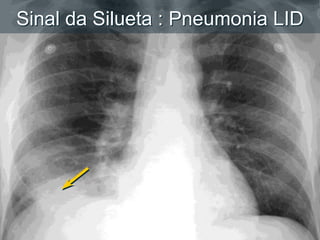

Silhouette Sign: RLL PneumoniaSinal da Silueta : Pneumonia LID

Porque nós vemoso que vemos:  Estruturas são visíveis em uma radiografia devido a justaposição de duas estruturas de diferentes densidades.  criando uma interface  Sinal da Silueta Perda de uma interface esperada  Nenhuma borda entre duas estruturas pode ser vista quando a densidade destas são similares Differential X-Ray Absorption

Silhouette Sign: RLLPneumoniaSinal da Silueta : Pneumonia LID